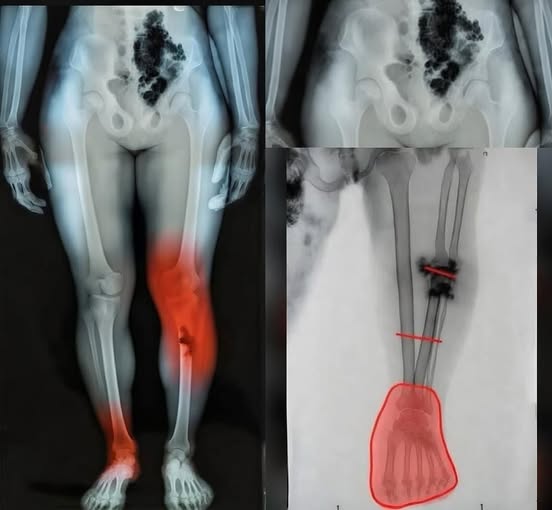

Wichtiges Warnzeichen für Krebs, das man nur nachts erkennen kann

Krebs ist eine verheerende Krankheit, und im Jahr 2025 werden in den Vereinigten Staaten unglaubliche 618.120 Menschen daran sterben. Wir alle kennen jemanden, der betroffen ist – deshalb sind Aufklärung und Früherkennung so wichtig. Erschreckenderweise überlebt nur die Hälfte aller…